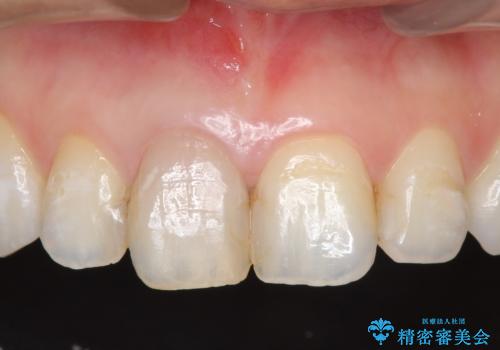

- 右上1番目の歯の変色が気になると来院された方の症例です。

検査の結果、右上1の歯は失活(歯の神経が死んでいること)していたため根管治療を行いました。

その後オールセラミッククラウン(スペシャル)による補綴を行いました。

なお隣在歯の樹脂は今後治療していく予定です。